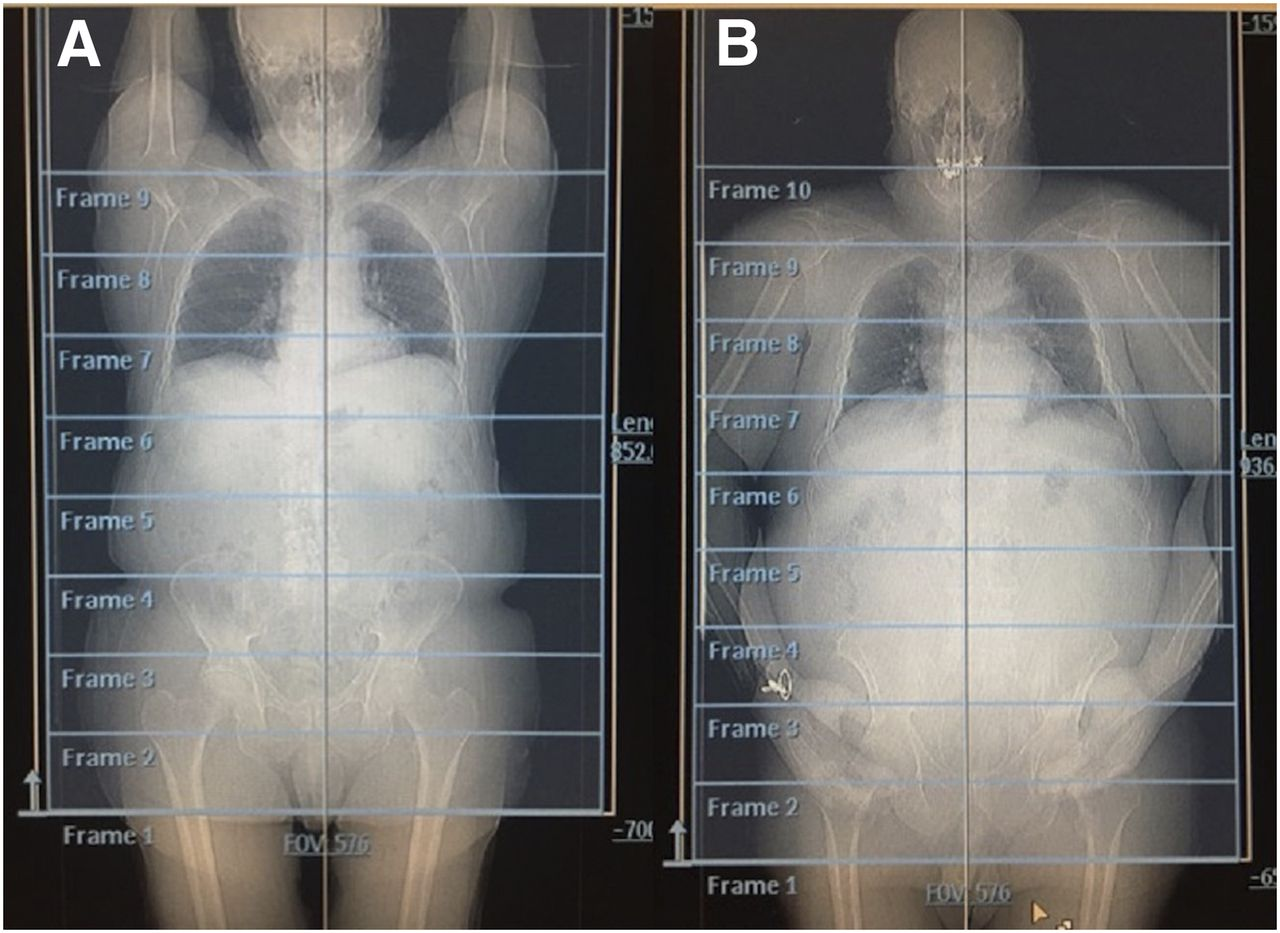

Breakdown what PET/CT is a combination of (what each part specifically scans)

PET – scans the patient’s physiology

CT – scans the patient’s anatomy

What is the skull-base to mid-thigh acquisition?

Most common acquisition for PET imaging

We would start scanning the patient from their eyes → end at their thighs

When would we perform a whole body acquisition?

If the patient has melanoma – want to image cancer from head-to-toe